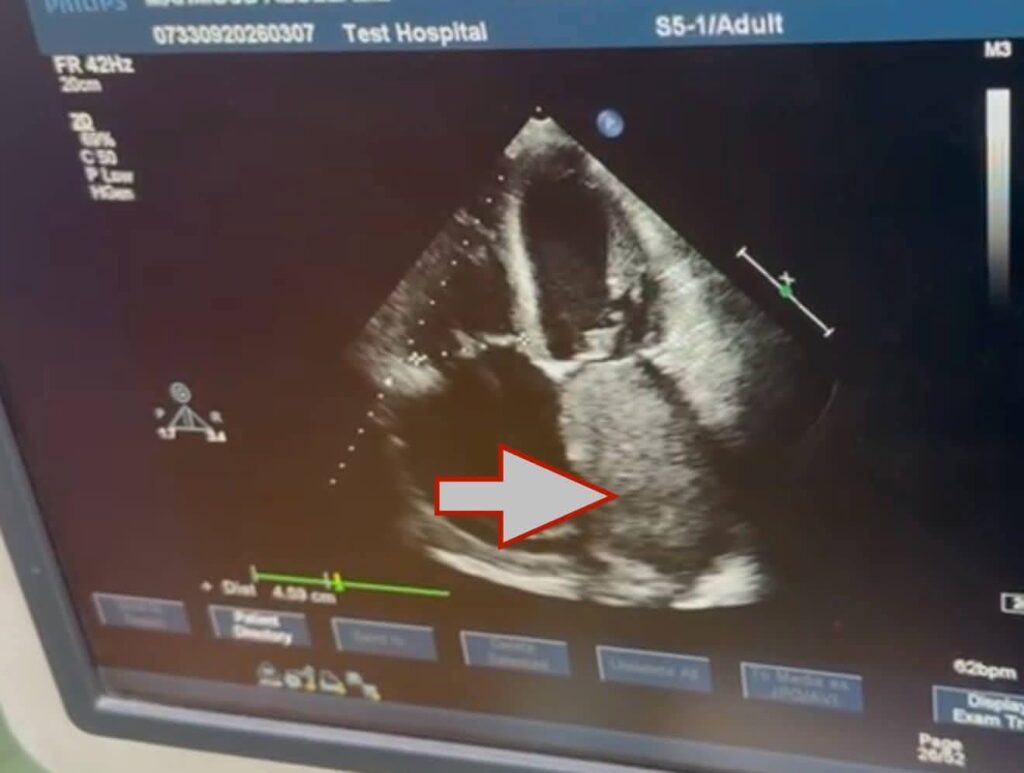

جدير بالذكر، أن الورم الذي تم استئصاله هو من نوع Cardiac Myxoma، وهو من الأورام القلبية النادرة التي تنشأ داخل حجرات القلب، وقد تسبب في انسداد شديد بفتحة الصمام الميترالي أثناء تدفق الدم، ما أدى إلى ارتفاع ملحوظ في ضغط الشريان الرئوي، نتج عنه ارتجاع شديد بالصمام الثلاثي الشرفات، إضافة إلى تضخم بالأذين الأيسر وحدوث ذبذبة أذينية.

واستغرقت الجراحة نحو أربع ساعات، تمكن خلالها الفريق الجراحي من استئصال الورم بالكامل مع قاعدته من الحاجز الأذيني، ثم إعادة ترميم الحاجز الأذيني باستخدام الغشاء التاموري، كما تم إجراء إصلاح جراحي للصمام الثلاثي الشرفات لعلاج الارتجاع الناتج عن ارتفاع ضغط الشريان الرئوي، وقد خرج المريض من الجراحة بحالة مستقرة، واستعاد وعيه بالكامل، ويتمتع الآن بتحسن ملحوظ في حالته، مع استمرار المتابعة الدقيقة لحالته حتي اكتمال الشفاء.